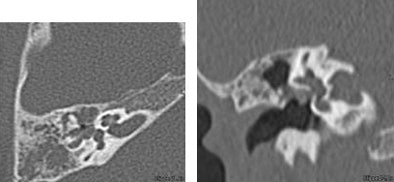

In an example of a 6-year-old with congenital cholesteatoma, thin-section axial images (0.5-mm collimation) were acquired at 100 kVp and 100 mAs, and viewed on isovoxel coronal reconstructions.

| Axial (left) and coronal (right) images of a 6-year-old with congenital cholesteatoma were acquired on a 16-slice MDCT scanner (Aquilion, Toshiba America Medical Systems, Tustin, CA) examined using isovoxel coronal reconstructions. All images courtesy of Dr. S. Bruce Greenberg. |